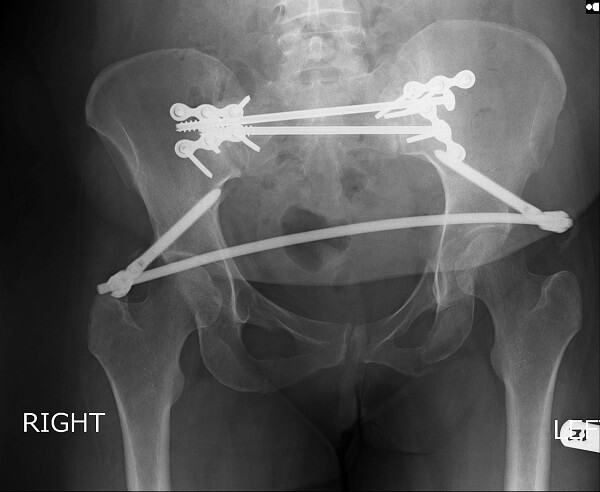

- Cố định xương chậu với thiết bị hỗ trợ được đưa từ ngoài vào như thanh nẹp kim loại, ốc, vít.

- Phẫu thuật mở và cố định ở bên trong. Các mảnh xương di lệch được đưa về đúng tư thế, và bác sĩ cố định xương với các dụng cụ gắn ở mặt ngoài của xương.